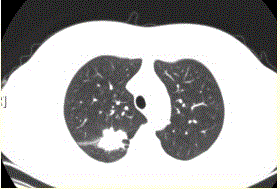

问题 患者女,54岁,无症状,常规体检透视时发现右上肺阴影。既往无结核病史。体格检查阴性。CT结果如下图。 最易出现分叶状边缘的肺癌类型是

选项 A.鳞癌 B.腺癌 C.未分化癌 D.肺泡癌 E.转移性肿瘤 F.肺类癌

答案 B

解析 B